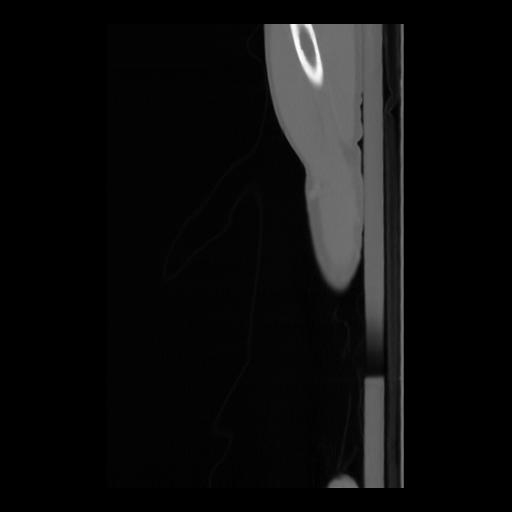

36 CUERPO,CE,Sagittal,3.000,CUERPO,Sagittal,